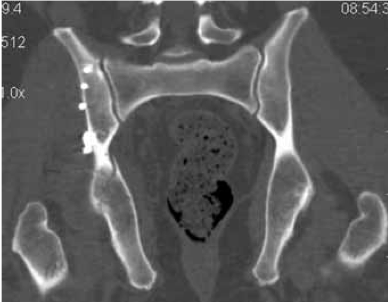

Как основной метод лечения, без стабилизации переднего полукольца таза, остеосинтез заднего комплекса винтами (рис. 1) выполнен у 196 пациентов. Из них открытые переломы встречались у 15 (7,7 %) и были представлены в 12 случаях разрывами мочевого пузыря, в 3 - разрывами уретры. У 161 пациента отмечались повреждения типа В, у 35 - типа С, у 124 - унилатеральные, у 72 - билатеральные. Повреждения переднего полукольца таза были представлены у 3 пациентов разрывами лонного сочленения, у 193 - переломами ветвей лонных костей. Разрыв КПС как основное повреждение заднего комплекса таза встречался у 75 пациентов, переломы подвздошной кости и крестца - у 121.

Рисунок 1. Рентгенограммы пациентки Б. 31 года, повреждение тазового кольца 61-В1: a) до реконструкции; b) после остеосинтеза заднего комплекса винтом с каналом 7,3 мм